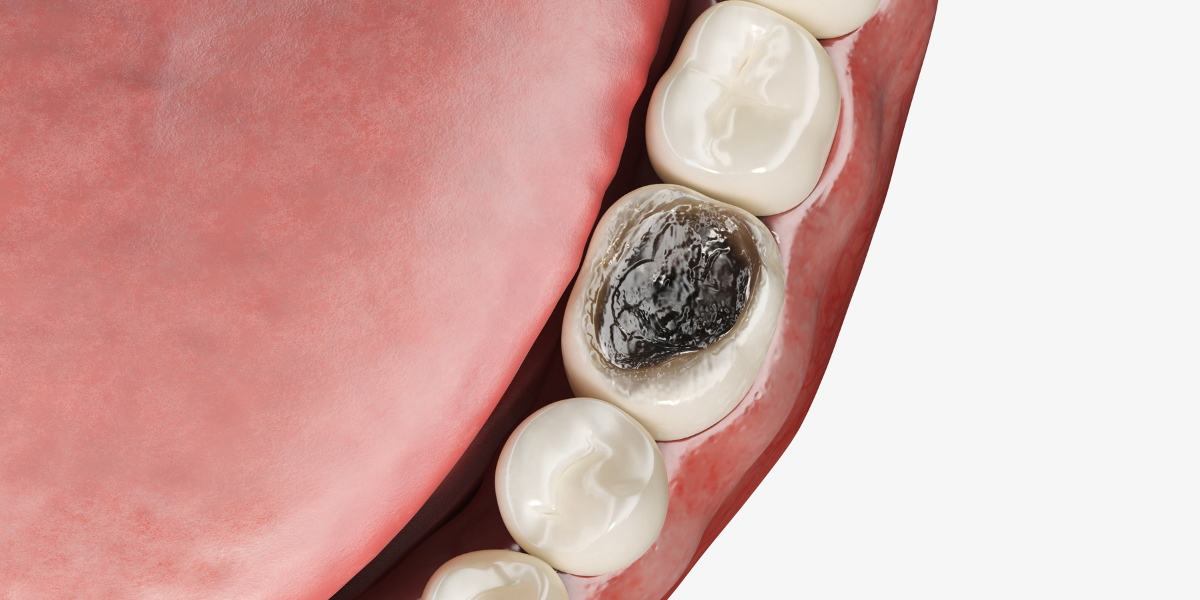

Dentin is a calcified (calcium carbonate or some other insoluble calcium compounds) bodily tissue that is protected by the tooth’s enamel. 70% of dentin is composed of the mineral hydroxylapatite, 20% is organic material and 10% is water. Everyone’s dentin is shade of yellow but the intensity varies per person which is why after teeth whitening treatments some never achieve the desired level of whiteness.

Dentin is a bone like structure however is soft in comparison to actual bone. The tooth is composed primary, secondary, and tertiary dentin. The outer layer is the primary, the secondary layer of dentin is produced after the root of the tooth has been fully developed and the tertiary dentin is a response to a stimulus. All three types of dentin are vital to the longevity of the tooth.